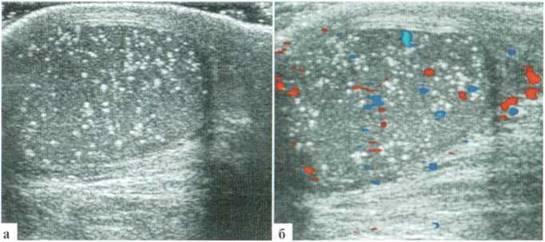

La microlithiase est une condition médicale caractérisée par la présence de petits dépôts de cristaux ou de calculs minuscules, généralement composés de sels minéraux tels que le calcium, à l'intérieur de certaines parties du corps. Cette condition est le plus souvent associée aux testicules et aux reins, bien qu'elle puisse également se produire dans d'autres organes.

La microlithiase testiculaire et rénale est une condition caractérisée par la présence de petits dépôts de cristaux ou de calculs minuscules dans les testicules et les reins. Les causes de cette condition peuvent varier en fonction de la localisation des calculs. Voici quelques-unes des causes possibles de la microlithiase testiculaire et rénale :